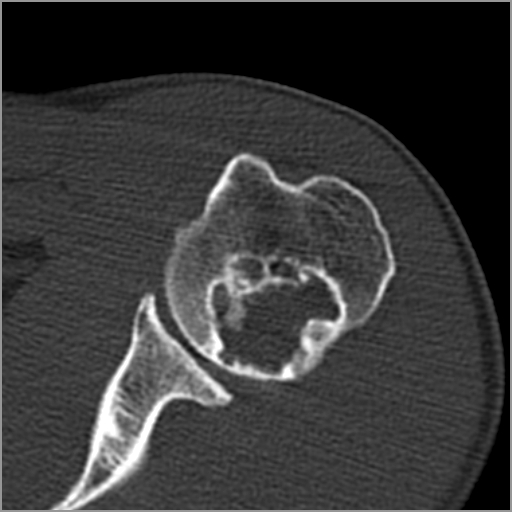

以下是引用zxd95在2008-7-19 18:45:00的发言:[br]囊性病灶边缘硬化、皮质变薄但连续——提示生长时间长、良性病变——考虑左肱骨头骨囊肿。[br]

以下是引用杀毒软件在2008-7-19 18:55:00的发言:[br]考虑:骨巨细胞瘤可能性大